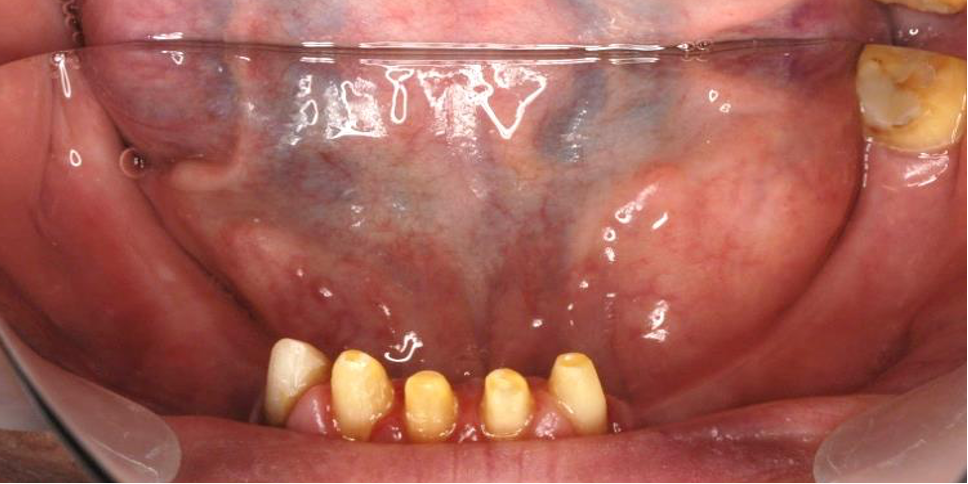

術前

ご来院いただいたときには、複数の欠損があるのと同時に重度の虫歯が進行していました。